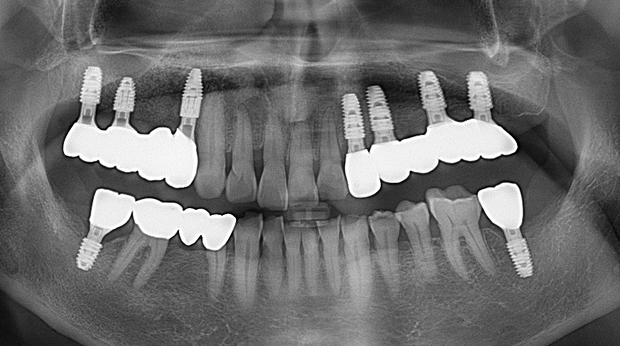

임플란트와 사랑니 발치는 외과적 시술로 잇몸을 절개하는 외과적 시술은

짧으면 짧을 수록 시술 후 붓기와 통증이 최소화됩니다.

치과의사 경력 14년차 구강외과 전문의가 빠르고 안전하게, 아프지 않게 수술해 드립니다.

치과경력 14년차 구강외과 전문의

연세대학교 치과대학 구강외과 임상 조교수